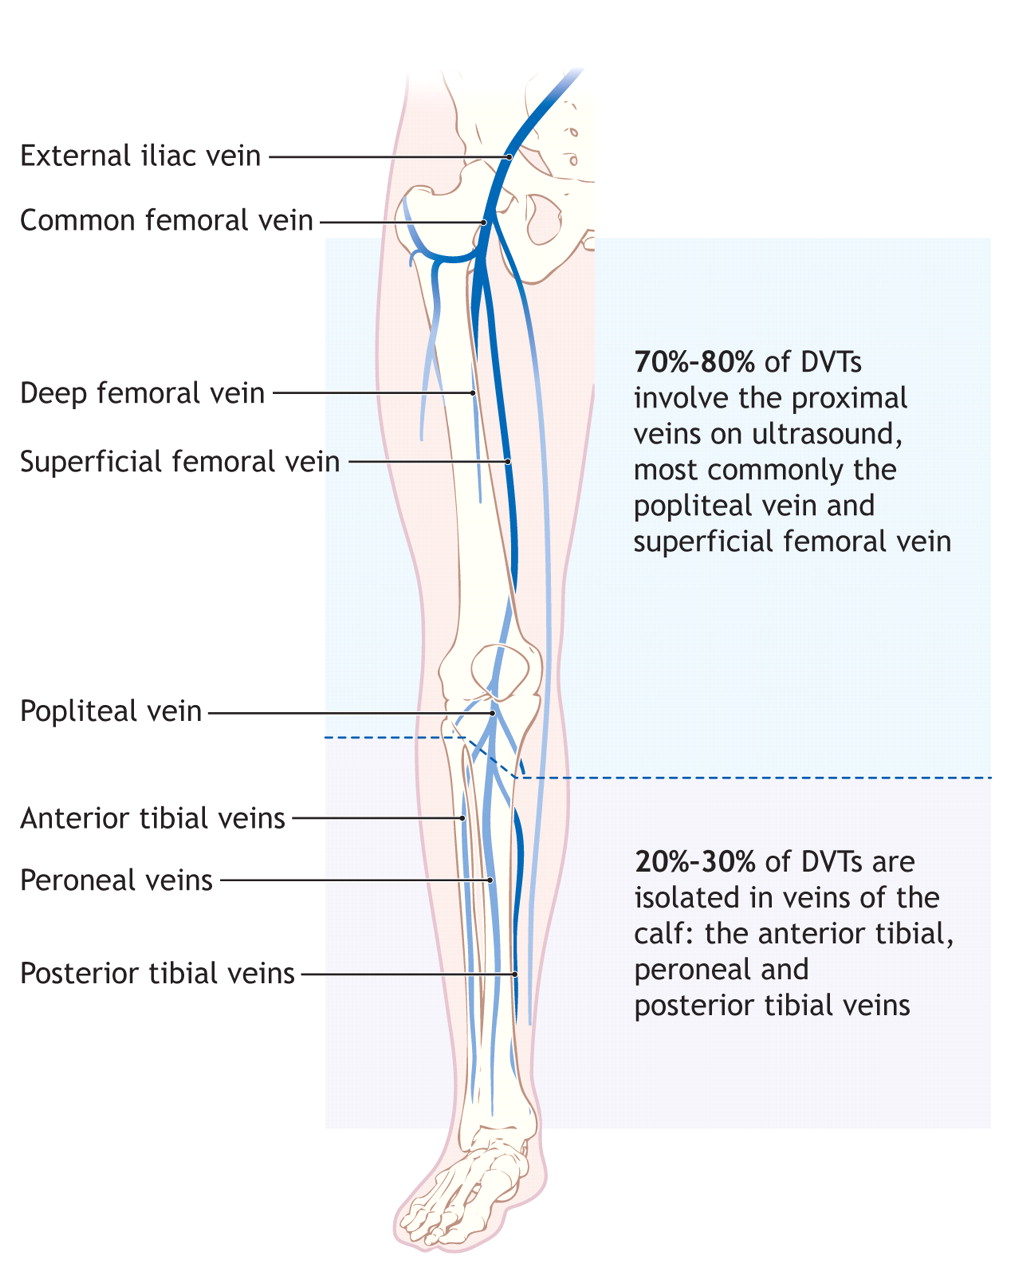

Diagnosis And Treatment Of Deep-vein Thrombosis | CMAJ

www.cmaj.ca

www.cmaj.ca

vein thrombosis treatment cmaj diagnosis 1087

Deep VT Introduction And Diagnosis | Thrombosis Adviser

www.thrombosisadviser.com

www.thrombosisadviser.com